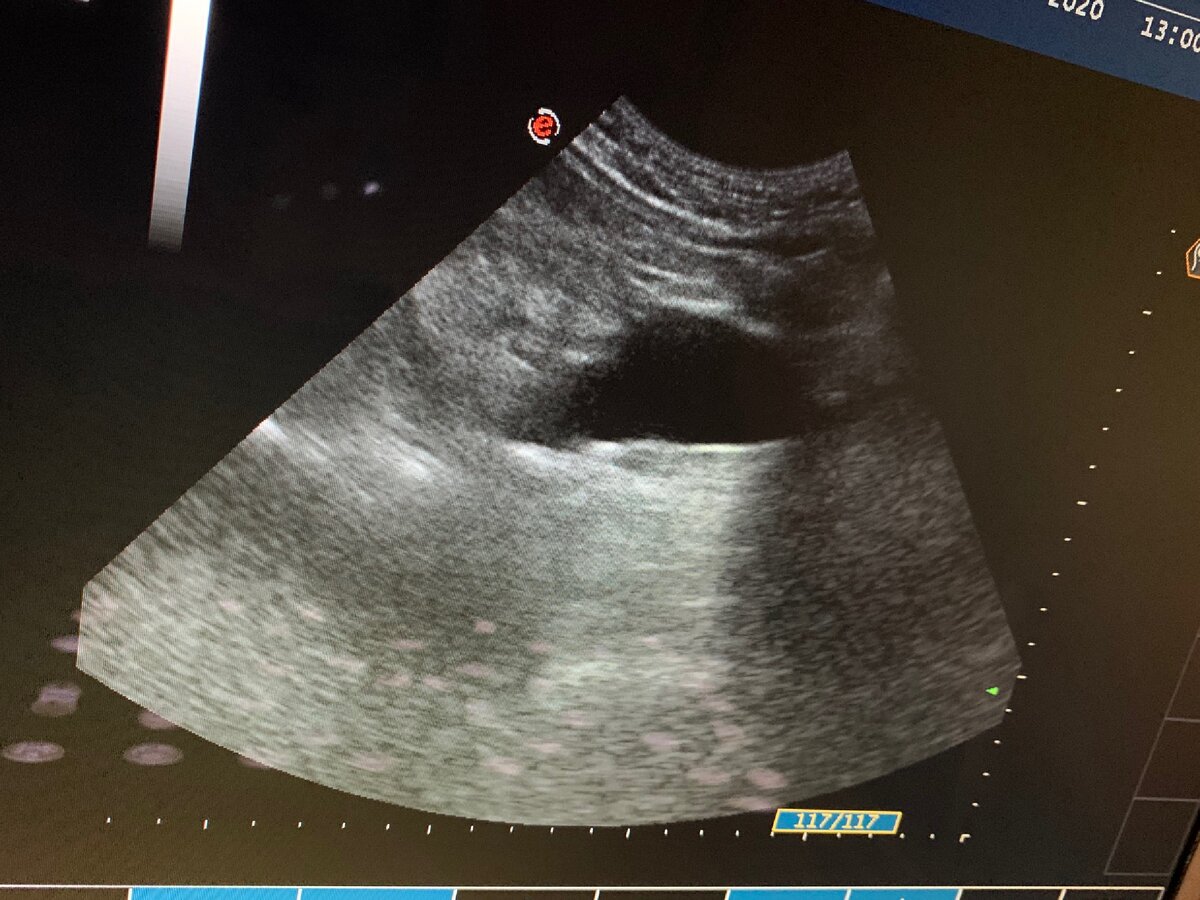

Признаки аневризмы на УЗИ

Чтобы своевременно выявить аневризму брюшного отдела аорты и тем самым снизить риски ее разрыва, мужчинам старше 60 лет, курящим людям, страдающим атеросклерозом и гипертонией, а также при семейном анамнезе аневризмы, рекомендуется выполнить УЗИ органов брюшной полости с оценкой диаметра аорты.

Если выявляется аневризма диаметром менее 5 см, то риск ее разрыва минимален и обычно данное расширение сосуда требует динамического проведения УЗИ каждые полгода.

При размерах аневризмы более 5 см врач может назначить КТ (компьютерную томографию) органов брюшной полости и рекомендовать хирургическое лечение. Это связано с повышением риска разрыва аневризмы.